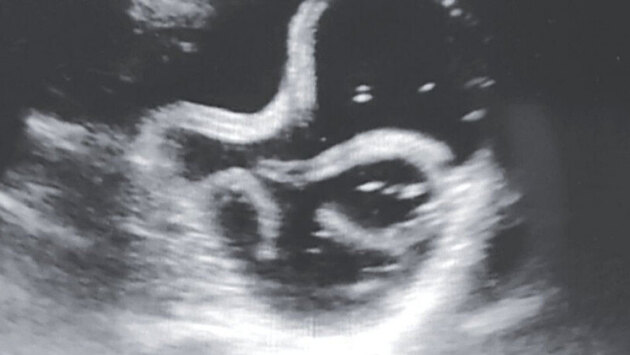

Согласно медицинскому отчету, опубликованному в The New England Journal of Medicine, 20-летний неназванный мужчина из Нью-Дели в Индии был госпитализирован с жалобами на сильную боль в животе, диарею и рвоту. Мужчина ранее был здоров. Анализ крови показал повышенный уровень лейкоцитов. Также обнаружился повышенный уровень гемоглобина – белка в крови, переносящего кислород. Все это указывало на различные заболевания: от обезвоживания до рака крови. Медицинские работники провели ультразвуковое исследование нижней полой вены – большой вены около желудка – чтобы определить уровень жидкости в крови. Когда они это сделали, увидели странные трубки, извивающиеся в кишечнике. Медики сразу же взяли образец стула у пациента, чтобы проанализировать его на наличие паразитов. Они обнаружили яйца Ascaris lumbricoides – одного из наиболее распространенных паразитирующих червей, которые живут внутри человека. По данным Центров по контролю и профилактике заболеваний, Ascaris lumbricoides живет в кишечнике почти у миллиарда людей во всем мире. Эти жуткие паразиты могут достигать в длину до 35 сантиметров. Обычно черви попадают в человека через поедание яиц, которые находятся на грязных овощах и фруктах. Инфицированные пациенты почти не чувствуют симптомов. К счастью, в описанном случае мужчина выздоровел после приема противопаразитарного препарата под названием альбендазол. Спустя сутки его выписали из больницы, а через две недели он рассказал медицинским работникам при повторном визите, что паразиты вышли со стулом.